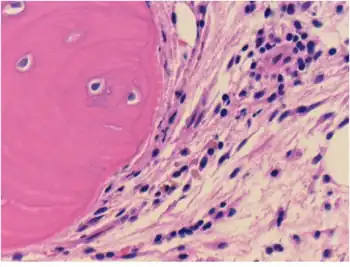

| Connective tissue with mild infiltration by mononuclear inflammatory cells | |